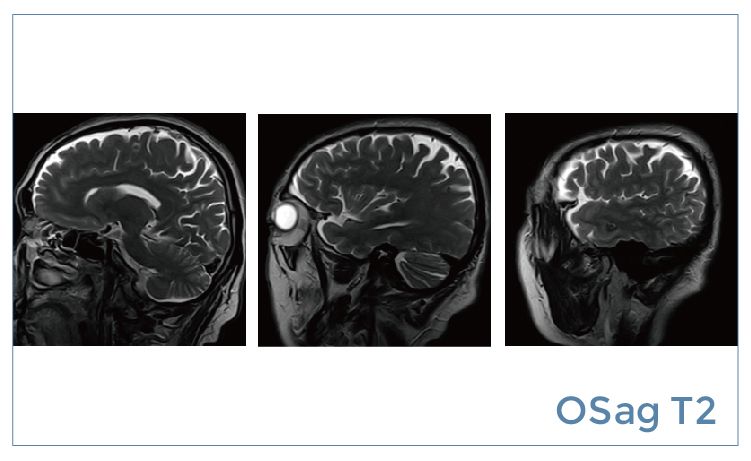

【朗润影像档案】20190614磁共振影像病例结果讨论

【朗润影像档案】磁共振影像病例分享(编号20190614)